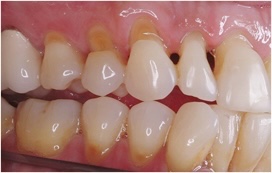

💡 핵심 요약: 치아와 잇몸이 맞닿는 ‘목 부분(치경부)’이 쐐기 모양으로 움푹하게 파여 상아질이 노출되면서 시린 통증을 유발하는 질환입니다.

보통 치아는 단단한 법랑질이 감싸고 있지만, 치경부는 구조적으로 법랑질이 얇고 힘이 집중되는 취약한 부위입니다. 이곳이 패이게 되면 외부 자극이 신경에 직접 전달되어 다음과 같은 증상이 나타납니다.

- 심미적 저하: 잇몸 라인이 패여 보여 치아가 길어 보이거나 형태가 변형되어 보입니다.